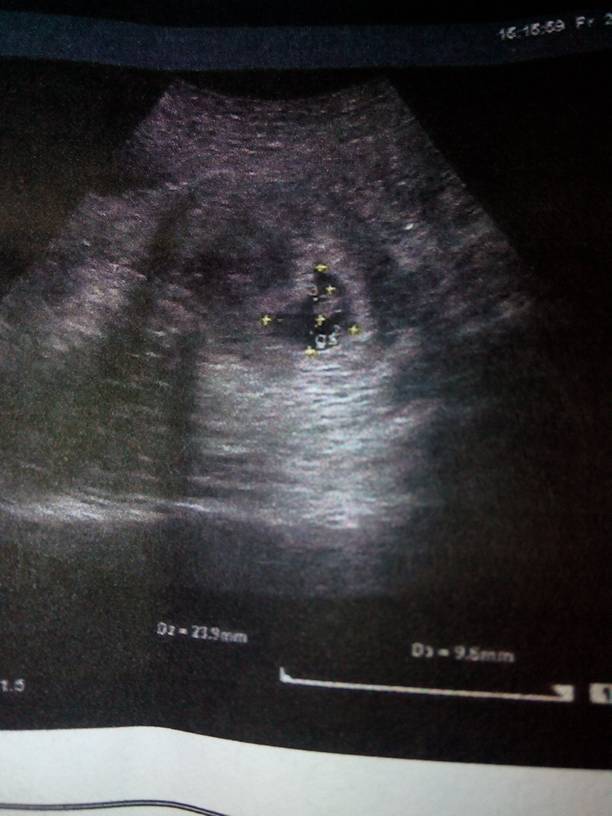

宝妈,帮我看看男女 宝妈,帮我看看男女 点击展开 蓉姐 2014-10-26 11:10 为您推荐: 其他回答 那是不科学的说法,,,, 可爱优优6688 2014-10-26 16:47 这样是判断不出来的,没有科学依据,另外,宝妈保持平常心吧,男孩女孩都是宝! 鲤鱼妈 2014-10-26 11:47 哦了解,想要男宝 那一抹阳光、 2014-10-26 11:44 看不出.. 辣椒泡菜 2014-10-26 11:35 还看不出来 贱人待我长发及腰勒死你_pDRe 2014-10-26 11:23 加载更多 相关问题 宝妈们…帮我看看是女儿不? 那个宝妈会看男女,帮我看看,预产期是1月20